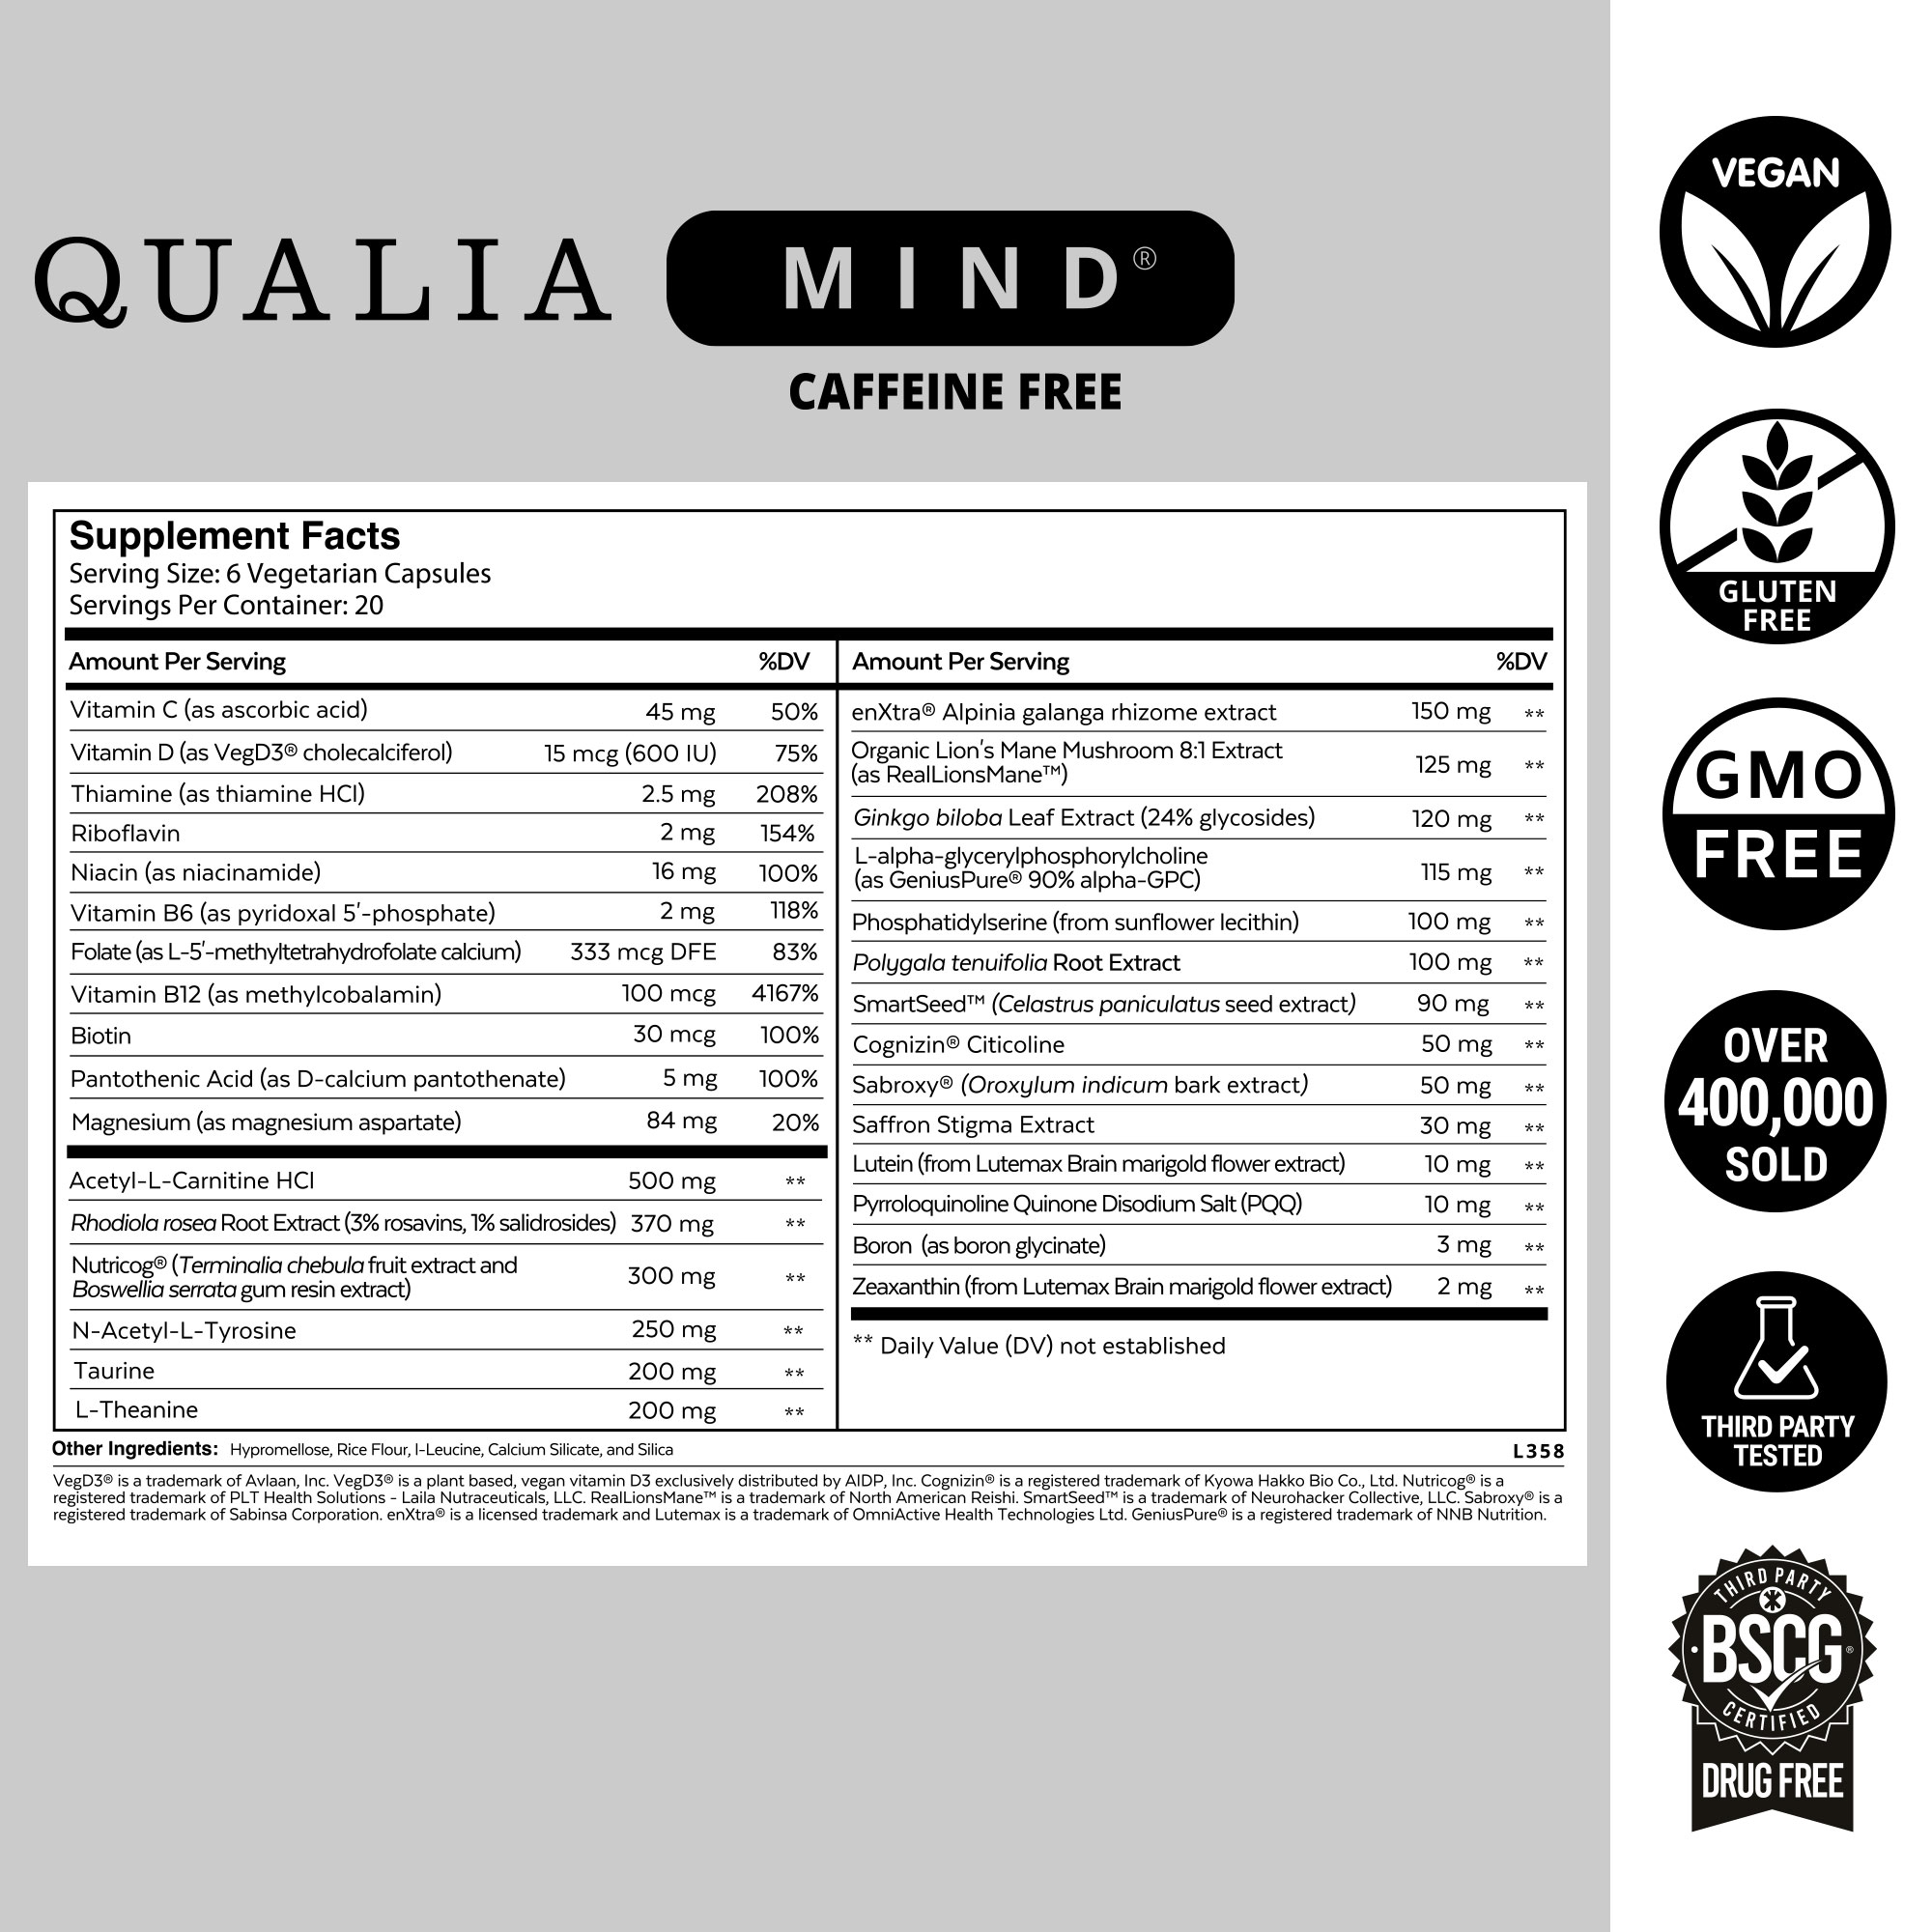

Sabroxy® (Oroxylum indicum bark extract) is made from the dried bark of the Indian trumpet tree/ (Oroxylum indicum). It supports healthy brain-derived neurotrophic factor (BDNF) function, helping to maintain neurological health and nerve functions. Sabroxy contains a flavonoid called oroxylin-A that supports healthy dopamine signaling which supports motivation and focus.*indirectly supports the healthy release of neurotransmitters like dopamine and serotonin.*

Cognizin® A clinically studied source of choline (found in various animal products and vegan foods such as nuts and cruciferous vegetables) and cytidine. It supports healthy acetylcholine production, an important neurotransmitter involved in attention, concentration, learning, memory, and neuroplasticity.*

Phosphatidylserine (from sunflower lecithin) is a phospholipid from sunflower lecithin, and brain-essential nutrient. It is a major phospholipid in the brain, supporting healthy membrane and neurotransmitter signaling, especially in parts of the brain related to memory functions.*

Acetyl-L-Carnitine HCl: an acetylated form of L-carnitine. This form of carnitine crosses the blood-brain barrier and is the preferred form for use in brain and nervous system support. It supplies carnitine and acetyl groups that collectively support the healthy production of acetylcholine neurotransmitter molecules, brain energy production, and neuroprotective functions.*

N-Acetyl-L-Tyrosine: N-acetyl-L-tyrosine (NALT) supplies the amino acid L-tyrosine, which is a building block for dopamine and catecholamine neurotransmitter molecules involved in supporting motivation, focus, and executive functions.*

Taurine: one of the most abundant amino acids in the brain and eyes, where it supports brain health, hearing, and vision. It’s involved in promoting long-term potentiation, healthy GABA and glycine neurotransmission, optimal function fo brain-derived neurotrophic factor (BDNF), neuronal mitochondrial function, neuroprotection, and photoreceptor cell visual function.*

L-Theanine: an amino acid found in the leaves used to make green and black teas. It promotes activity in the alpha frequency band; this frequency of brain waves is characteristic of attention and relaxation of the mind without drowsiness. L-theanine promotes focused attention, mental alertness, and calm, relaxed energy.*

L-alpha-Glycerylphosphorylcholine (alpha GPC): a choline form found in the brain. It supports healthy acetylcholine production, an important neurotransmitter involved in attention, concentration, learning, memory, and neuroplasticity. Alpha GPC also supports phospholipid metabolism in the brain, which is important for keeping brain cells healthy.*

L-alpha-Glycerylphosphorylcholine (alpha GPC): a choline form found in the brain. It supports healthy acetylcholine production, an important neurotransmitter involved in attention, concentration, learning, memory, and neuroplasticity. Alpha GPC also supports phospholipid metabolism in the brain, which is important for keeping brain cells healthy.*

EnXtra®: s a clinically studied and standardized rhizome extract from the Alpinia galanga plant. It’s a plant in the ginger family native to Southeast Asia where it’s used as a food and herb. The research emphasis in human studies of enXtra® has been for support of alertness and focus.*

Pyrroloquinoline Quinone disodium: also known as (PQQ) is a vitamin-like antioxidant compound. It supports optimal activity, blood flow, and oxygen metabolism in areas of the prefrontal cortex involved in thinking, attention, and memory. PQQ also supports healthy energy production, mitochondrial health, and cellular protection and repair functions.*

Boron (as boron glycinate): Boron is a trace mineral. It is best known for supporting bone health and optimal sex hormone levels. Studies suggest it may also be a brain-essential nutrient. Adequate dietary intake of boron is needed to support healthy brain electrical activity and cognitive performance, especially in areas related to attention and memory.*

Vitamin C (as ascorbic acid): Vitamin C is a brain-essential nutrient. It’s best known for its neuroprotective support as an antioxidant. Vitamin C is involved in the conversion of dopamine to noradrenaline and helps dampen neuronal over-stimulation by glutamate. It also promotes the regulation of catecholamines and acetylcholine from synaptic vesicles and the formation of myelin.*

Vitamin D3 (as cholecalciferol from VegD3®): VegD3® is Vitamin D3 (cholecalciferol) produced from a non-GMO algal source. Vitamin D3 is a fat-soluble vitamin and a brain essential nutrient involved in the healthy growth and function of neurons by supporting brain‐derived neurotrophic factor (BDNF), glial‐derived neurotrophic factor (GDNF), nerve growth factor (NGF) and other neurotrophic factors. Adequate vitamin D3 is needed for healthy dopamine signaling, neuroprotective functions, and neuroplasticity.*

Thiamine (as thiamine HCl): Thiamine (B1) is a member of the B-complex vitamin family and a brain essential nutrient. It supports healthy brain energy metabolism, neuron health, neurotransmission, and adrenal gland function. Thiamin helps synthesize several neurotransmitters involved in focus, memory, motivation, and mood, including acetylcholine, dopamine, and GABA.*

Riboflavin: Riboflavin (B2) is a member of the B-complex vitamin family and a brain essential nutrient. It supports optimal brain energy production, the production of glutathione (a cellular antioxidant), and healthy adrenal function. Riboflavin is needed for myelin and is used in the metabolism of fats, which is critical in the brain since it is mostly made of fats.*

Niacin (as Niacinamide): Niacinamide (B3) is a member of the B-complex vitamin family and a brain essential nutrient. It supports healthy NAD+ levels, energy production, antioxidant defenses, and cellular repair and stress response functions. Vitamin B3 is critical for maintaining the health of the central nervous system (i.e., it’s neuroprotective).*

Vitamin B6 (as pyridoxal 5'-phosphate): Vitamin B6 is a member of the B-complex vitamin family and a brain essential nutrient. Pyridoxal 5'-phosphate is a coenzyme (i.e., active) form of vitamin B6. It supports the healthy production of brain glucose and energy metabolism. Vitamin B6 is directly or indirectly needed for supporting the production of neurotransmitters related to motivation, focus, and mood, including acetylcholine, dopamine, GABA, and serotonin.*

Folate (as L-5'-methyltetrahydrofolate calcium): Folate (B9) is a member of the B-complex vitamin family and a brain essential nutrient. L-5'-methyltetrahydrofolate calcium is a coenzyme (i.e., active) form of folate. It supports the healthy function of brain and nerve cells, and is needed for the production of myelin. Folate is involved in promoting healthy dopamine, melatonin, noradrenaline, and serotonin, and supports healthy hearing, mood, and vision.*

Vitamin B12 (as methylcobalamin): Vitamin B12 is a B-complex vitamin and a brain essential nutrient. Methylcobalamin is the coenzyme (i.e., active) form of vitamin B12, and the preferred nootropic form. It supports the healthy function of brain and nerve cells, and is needed for the production of myelin. Methylcobalamin is involved in promoting healthyg dopamine, melatonin, noradrenaline, and serotonin, and supports healthy hearing and vision.

Biotin: Biotin (B7) is a B-complex vitamin and a brain essential nutrient. It supports healthy glucose metabolism, which is important because the brain is particularly sensitive to the delivery and metabolism of glucose. Adequate dietary biotin is also important for healthy dopamine neurotransmission.*

Pantothenic Acid (as calcium pantothenate): Pantothenic acid (B5) is a B-complex vitamin and a brain essential nutrient. It supports healthy brain energy production, the synthesis of neurotransmitters (most notably acetylcholine), the production of the myelin required for healthy nerve function, and adrenal function (it’s often referred to as the “anti-stress” vitamin).*

Magnesium (as magnesium aspartate): Magnesium (Mg) is a brain essential mineral. It is needed for the optimal production of dopamine and serotonin, and plays a role in supporting other neurotransmitters, including GABA and glutamate. Mg is also an essential factor in making and activating ATP (brain energy), nerve transmission, blood-brain barrier integrity, a healthy stress response, and hearing and vision.*